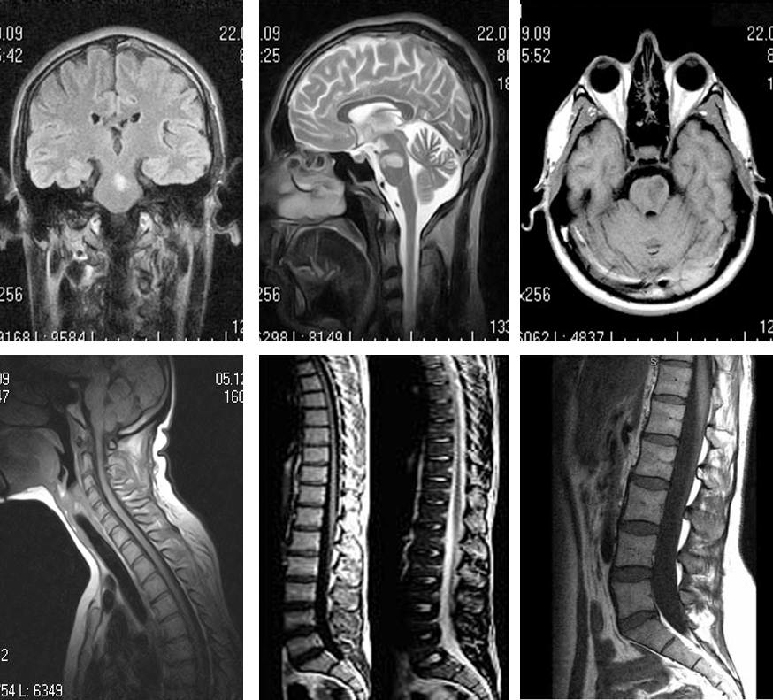

Демиелинизирующие заболевания мозга: МРТ изображения